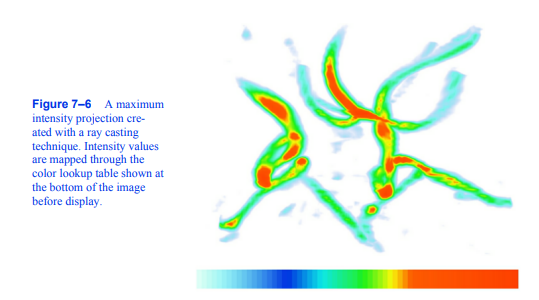

最大强度投影(MIP)可能是可视化体积数据的最简单方法。当涉及到有噪声的数据时,这种技术是相当宽容的,并且生成的图像提供了对底层数据的直观理解。这种方法的一个问题是,不可能从静止图像中判断出沿射线的最大值发生在哪里。例如,考虑图7 - 6所示的颈动脉图像。我们无法从这张静止图像中完全了解血管的结构,因为我们无法确定某些血管是在另一些血管的前面还是后面。这个问题可以通过生成显示数据旋转的小图像序列来解决,尽管对于并行摄像机投影,即使这个动画也会模糊。这是由于两个图像生成的相机

图7-6用射线投射技术创建的最大强度投影。强度值通过显示在图像底部的颜色查找表映射。

从相反的方向查看数据将是相同的,除了关于图像Y轴的反射。